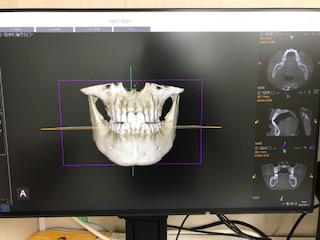

■ 3次元CTスキャンによる切開の無いインプラント手術 |

当クリニックではコーンビームCTスキャンを併用したインプラント手術を行っています。本CT撮影装置は3次元画像をコンピューター上で解析可能であるために、ほとんどのインプラント手術を切開無しで行うことが可能です。 CT撮影によるインプラントの位置決めを行いますので、インプラントの埋入には歯肉に小さな穴をあけるだけです。術中の痛みも殆んど心配ありません。 手術に伴う侵襲も少ないため術後の治りが早く、ほとんどの患者さんはインプラント手術の翌日に通常の日常生活をおくることが出来ます。

新世代CTの導入について

当クリニックでは以前よりCTを活用してまいりましたが、この度CTを新世代機種に更新しました。

1)インプラント治療の精度と安全性がより一層向上しました。

2)インプラン手術シュミレ−ション能力が向上しました。

3)親知らず抜歯等の口腔外科手術のプランニングが一層向上し、手術の安全性が向上しました。

4)その他歯科治療で多様な活用が期待されます。